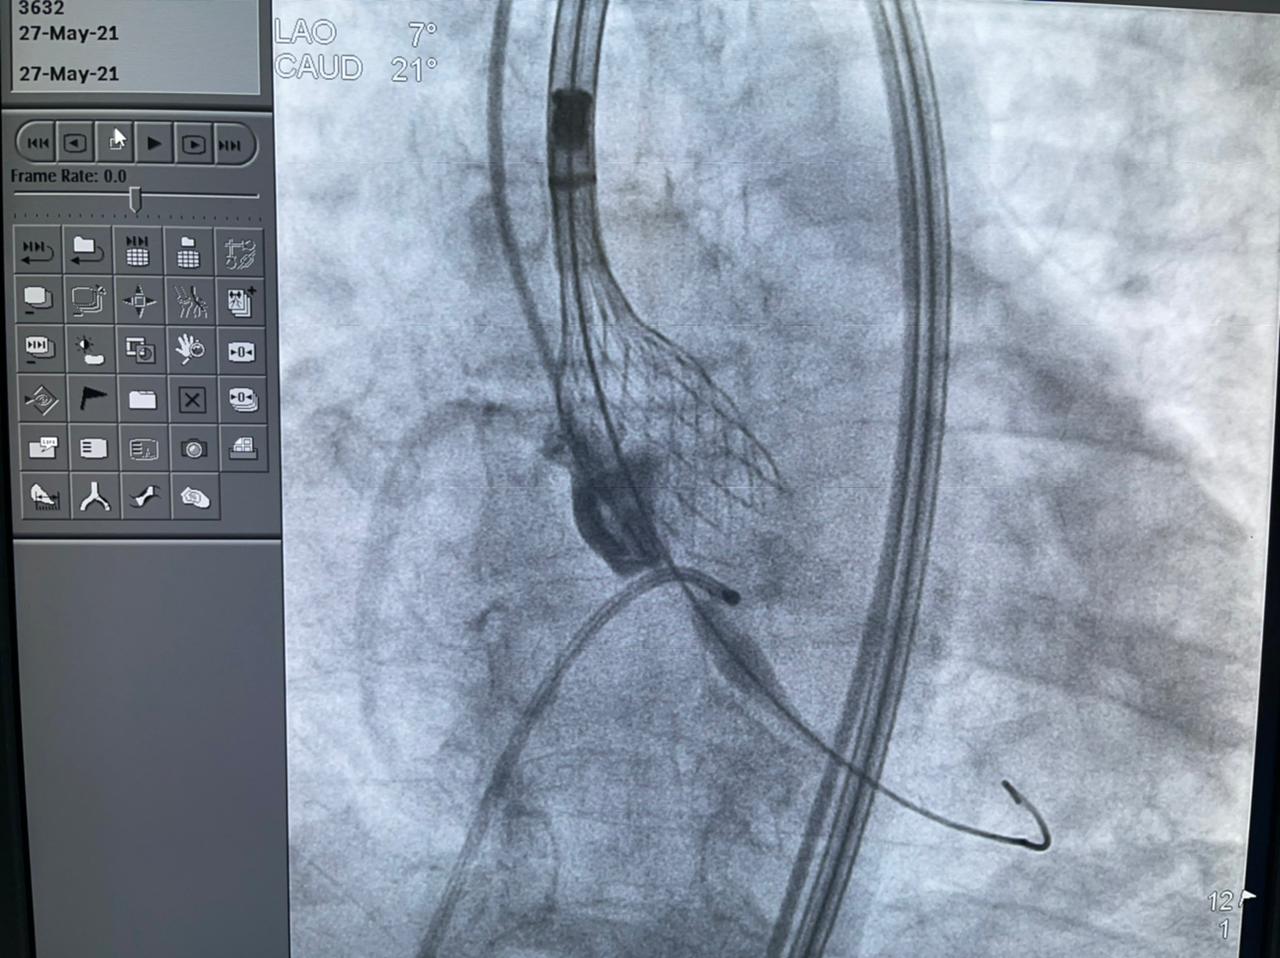

وأضافت الهيئة أن الحالة الثانية هي عملية زراعة الصمام الأورطي لمسنة تبلغ من العمر 78 عامًا، كانت تعاني من ضيق شديد بالصمام الأورطي، وتمت العملية بنجاح بعد أن كانت تعاني من تعب شديد وضيق بالتنفس وآلام بالصدر ونوبات إغماء، وتم إقرار علاج المريضة بعملية زراعة الصمام نظرًا لتقدم عمرها والضعف العام لحالتها الصحية، وتم إجراء العملية بتقنية التافي العالمية التي يتم بها تغيير الصمام الأورطي عن طريق القسطرة.

وتابعت الهيئة أنه قام بإجراء العمليات للمرضى الثلاثة في يوم واحد، فريق من أمهر الأطباء الأخصائيين والاستشاريين في علاج أمراض القلب والقساطر القلبية، يضم، الدكتور طارق رشيد أستاذ القلب والقسطرة وخبير حالات الانسداد المزمن للشرايين التاجية ورئيس قسم القسطرة القلبية بمستشفى النصر التخصصي، والدكتور ياسر صادق استشاري القلب وخبير القسطرة القلبية، الدكتور أمير البسطويسي استشاري جراحة القلب والصدر، الدكتور أحمد شبل استشاري القلب والقساطر التداخلية، الدكتور محمد علم الدين استشاري القلب والقسطرة العلاجية، الدكتور محمد لبيب استشاري جراحة الأوعية الدموية، وإخصائي علاج أمراض القلب والأوعية الدموية الدكتور معتز سلامة و الدكتور محمد عطا، أخصائي علاج أمراض القلب والقسطرة العلاجية الدكتور مصطفى رفعت، الدكتور أحمد عبد الرؤوف أخصائي التخدير بالمستشفى.

كما أشار الدكتور ياسر صادق إلى أن مصر أصبح لديها كفاءات بشرية، ولديها تقنيات وأجهزة تمكن من إجراء أصعب العمليات الدقيقة في مجال القلب، والتي من بينها عملية التافي، وذلك بمعايير عالمية تضاهي وتتفوق على الأرقام العالمية في المجال.